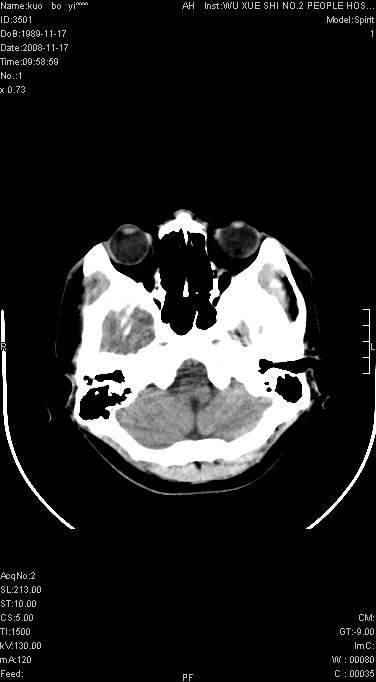

标题: CT16651:Ct平扫+增强脑瘤吗.请会诊 [打印本页]

标题: CT16651:Ct平扫+增强脑瘤吗.请会诊

右侧肢体无力一周

灶中央有厚环状高密度成分,顶叶皮质局部有显著的受压表现,多支持占位性病变,胶质瘤?淋巴瘤?转移?不知患者年龄多大,病史较短,不除外炎性

左顶叶较大范围水肿区,内见明显强化的片状 棉絮状组织,但占位效应不明显。多考虑:脑炎!

还是考虑原发脑胶质瘤,梗塞缺血水肿的低密度要同时累及皮、髓质并要符合动脉供血的区域分界特点,本例强化后见瘤体结节及向周围浸润生长的瘤血管都强化了,水肿广泛呈指状,占位效应使同侧脑皮质受压变薄、脑沟消失但因实质性的瘤体尚小所以中线无明显移位。不知各位同意这样分析吗?(转移瘤多为多处病灶)

首先考虑脑胶质瘤。有明显的左顶叶脑白质水肿,病变轻度占位效应,花环样强化,脑炎——影像不支持!